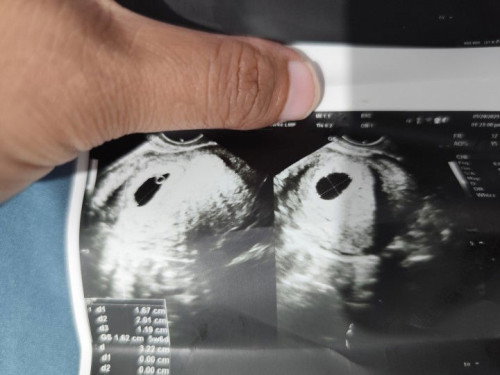

Ask ko ko lang may same experience ba Ng Ganto before Kasi nagkaroon ako Ng anembryonic pregnancy , I'm just scared if tutuloy BA ang baby if ganyang ultrasound, btw this is my first ultrasound today , it says I'm 5 weeks and 6 days since my bad experience na ako before I'm just scared to encounter the same scenario #AskingAsAMom #pregnancy